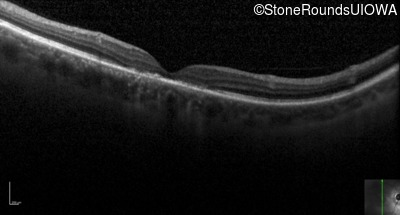

Optical Coherence Tomography - Right - 10/125 +1 sc

Exemplar / OCT Stack

OCT Stack

Optical Coherence Tomography - Left - 10/160 sc